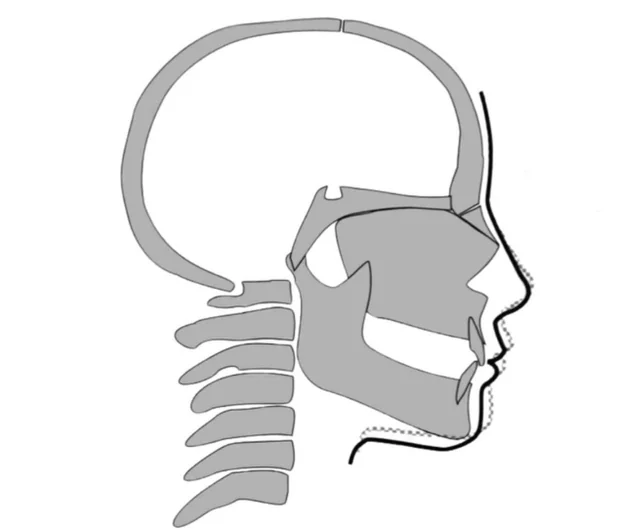

For reference here is what CCW can do, combined with a Bimax of course:

View attachment 4421320View attachment 4421319

Here is a skeletal graph of what it does:

View attachment 4421324

For reference here is what CCW can do, combined with a Bimax of course:

View attachment 4421320View attachment 4421319

Here is a skeletal graph of what it does:

View attachment 4421324